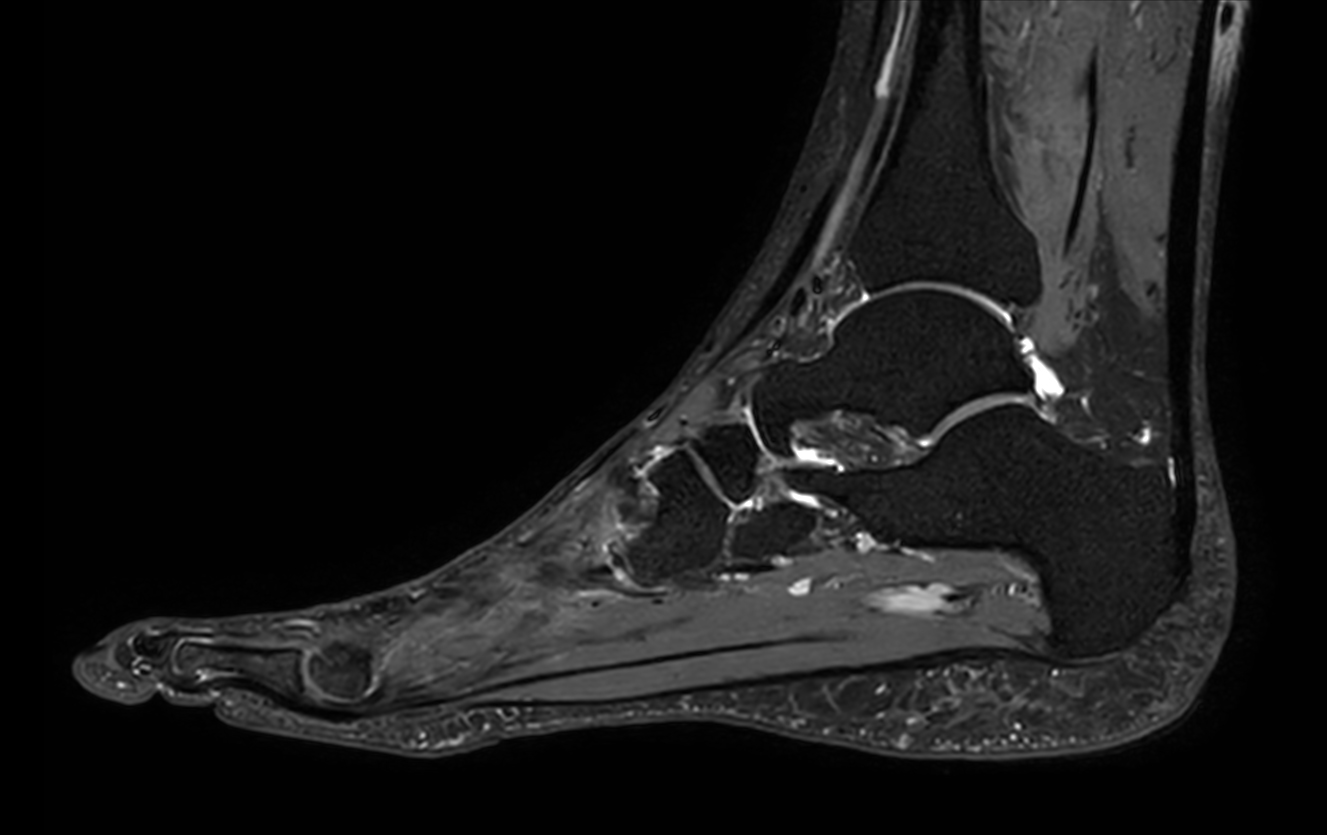

Sagittal 3D VIEW PDw SPAIR

-